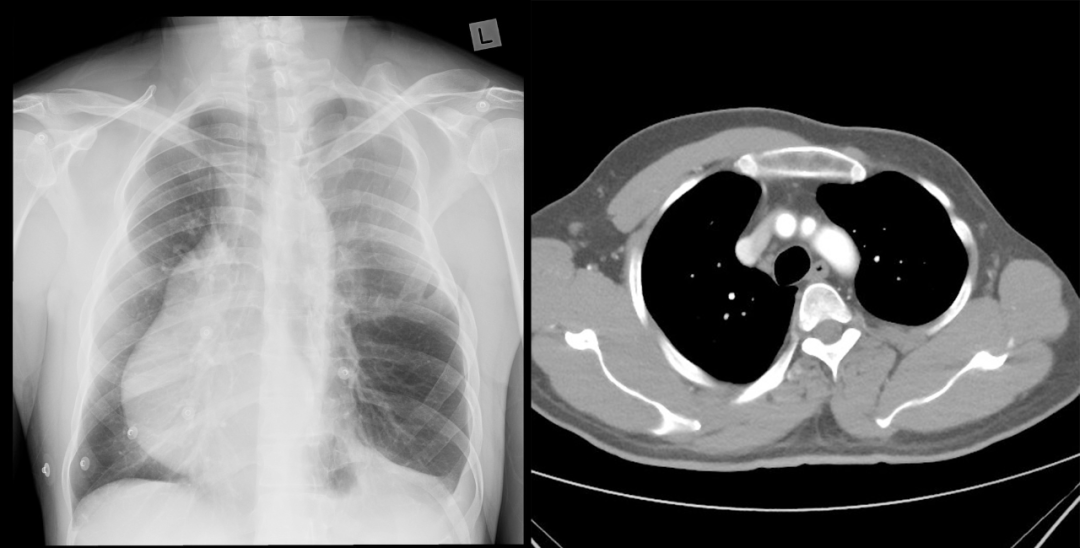

男,39 岁,体检肺 CT。

影像表现:右侧胸大肌及胸小肌缺如。

最终诊断为:部分型 Poland 综合征 (Poland syndrome)

影像学:主要表现为胸壁、肌肉、乳房及同侧上肢缺损或畸形的程度,并与健侧对比。3D 重建有利于更明确显示胸廓、肋骨及软组织畸形,本例右侧胸大肌及胸小肌缺如。